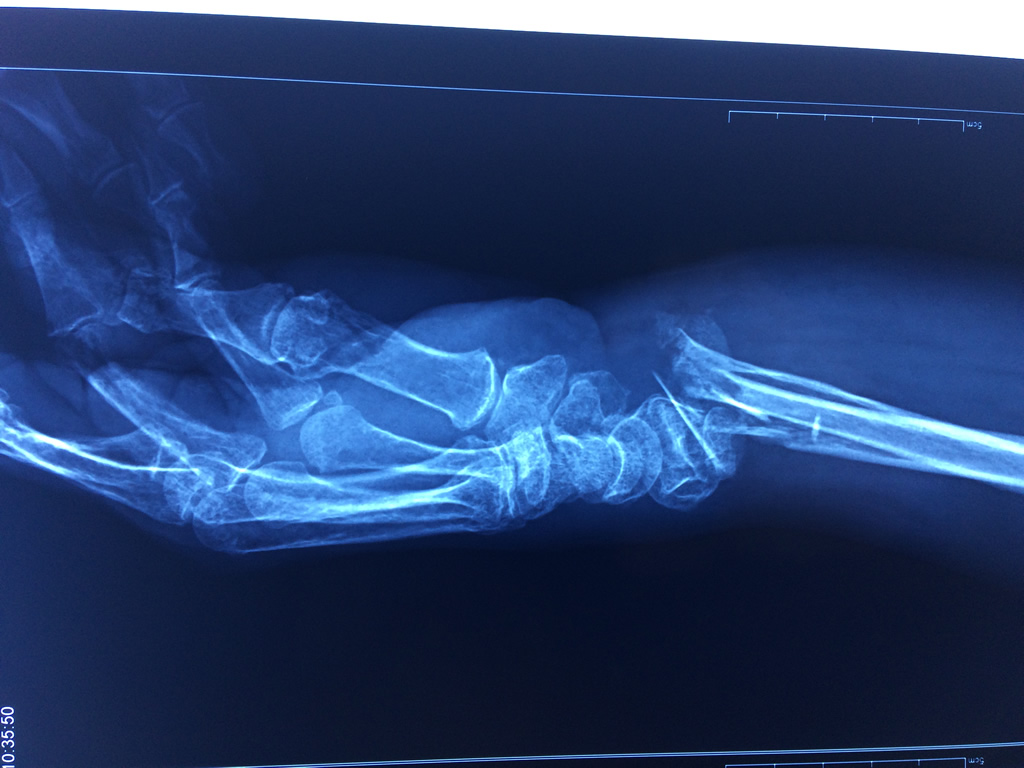

Cirugías de Muñecas

Los procedimientos más comunes en cirugía de la mano son aquellos destinados a reparar traumatismos, incluyendo lesiones de tendones, nervios, vasos sanguíneos, y articulaciones; huesos fracturados; y quemaduras, cortes, y otros daños de la piel.